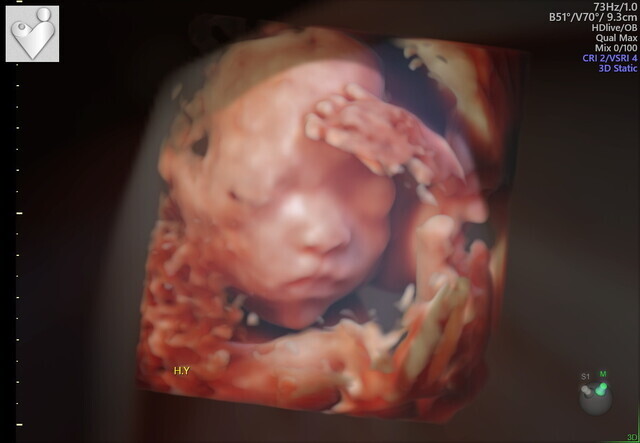

23週5日(23w5d・女の子)|misakikura さん(33歳)

まさかの足での敬礼。産婦人科の先生も、足で敬礼してる子はなかなかいないねって笑ってました。もっと前に撮ったエコーではここまで顔立ちハッキリしてなくわからなかったですが、、この時のエコーは鼻と口元が主人にそっくりでびっくり。主人に「似てるね」って話したら、「そうかなぁ?」って照れながら喜んでました。